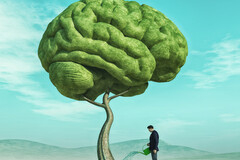

Déjouer la douleur chronique avec une approche psychologique révolutionnaire

Aider son cerveau à recoder différemment le message douloureux transmis par nos nerfs c'est possible ? C’est en résumé le parti pris de la « thérapie de reprogrammation » (Pain Reprocessing Therapy ou PRT) qui connait un succès grandissant aujourd’hui aux États-Unis. Cette approche innovante de la douleur, qui a notamment fait ses preuves dans le mal de dos chronique, n’est encore connue et utilisée que par quelques thérapeutes dans l’hexagone. Mais, bonne nouvelle : la ...